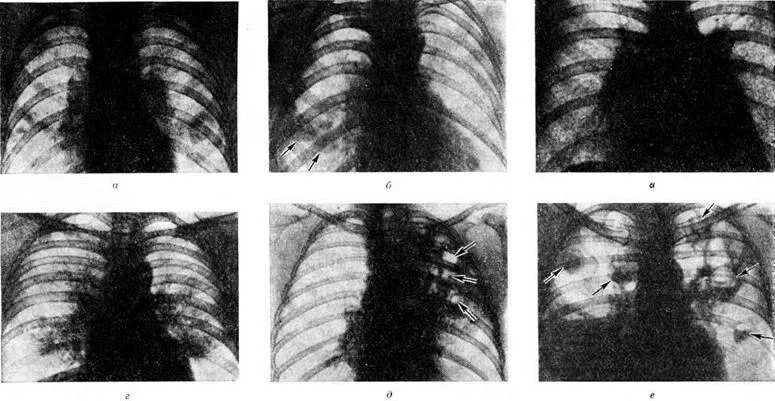

Сегментарная пневмония у взрослых что это значит